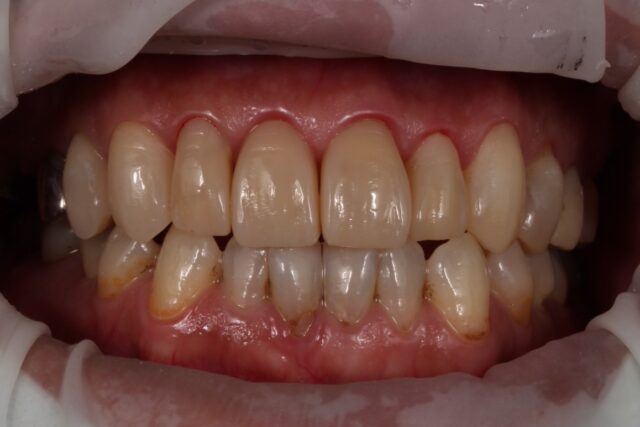

矯正なしで開咬を改善したケース

| 症状 | 元々開口傾向があり、前歯での咬合が十分に機能していない状態でした。 その後の治療を経て、前歯での咬合が困難となったため、機能改善を目的に治療へ |

| 治療法 | 右上4〜左上4(計8本)ダイレクトボンディング |

| 費用 | 約70万 |

| 通院回数 | 合計4回(週1程度) |

| 備考 | 費用面及び残存歯質の温存を考慮し、矯正治療や補綴処置ではなく、ダイレクトボンディングによる対応を選択した。 |